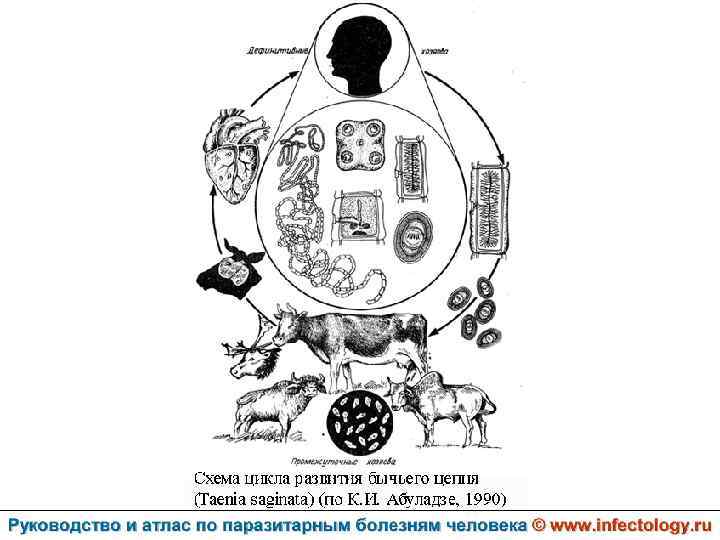

Тениаринхоз (шифр по МКБ 10 - B 68. 1) – антропонозный биогельминтоз с хроническим течением, характеризующийся преимущественно желудочно– кишечными расстройствами.